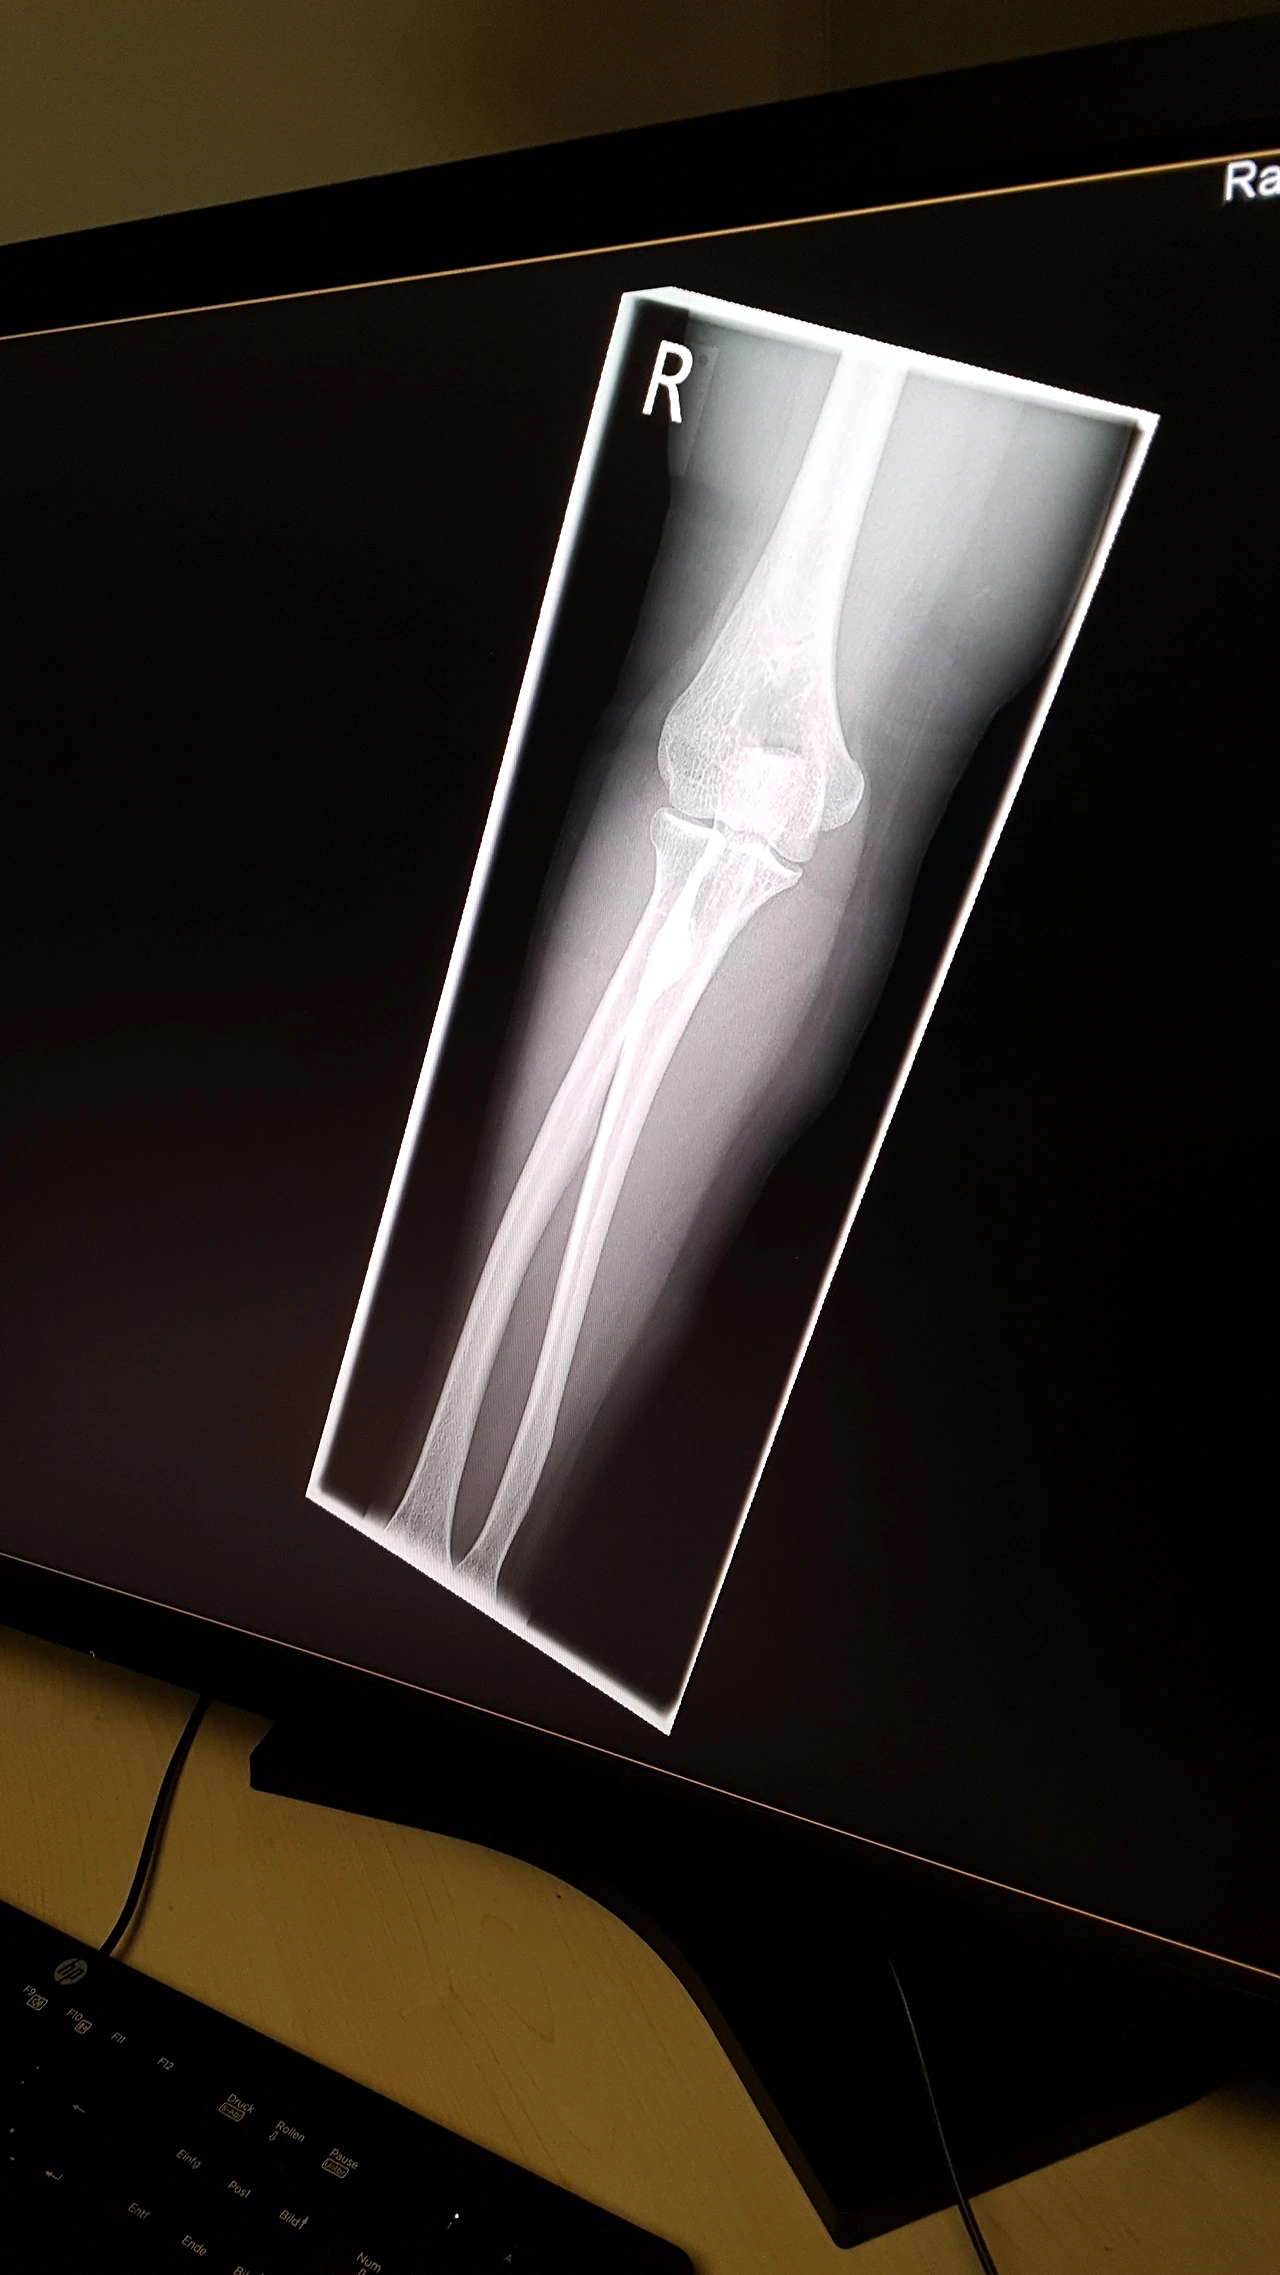

집으로 오던 날 그리스에서 넘어져서 다쳤던 오른팔이 시간이 지날수록 욱신욱신 더 아파왔다.

움직일 수 있는 것으로 보아 다행히 팔이 크게 부러진 것 같지는 않은데 통증이 계속됐다.

주말이라 급한 데로 우선 압박붕대를 감아 두고 있었지만 팔꿈치 뼈 밑으로 뽈록 하게 부은 것이 붕대 위에서도 만져질 만큼 혹처럼 부었고 팔을 최대한 움직이지 않고 가만히 앉아 있어도 아팠다. 결국 진통소염제를 복용했다. 웬만해선 약을 잘 먹지 않는 나로서는 드문 일이었다.

뼈가 부러진 것은 아니래도 금이 갔던 뭔가 문제가 있지 싶었다. 일단은 엑스레이를 찍어 보아야 할 것 같았다.

다행히 엑스레이 결과는 팔이 부러진 곳도 금이 간 곳도 없었다.

그런데 너무 세게 넘어지면서 타박상이 심해서 통증이 있었을 것이라는 것이 방사선과 닥터의 소견이었다.

며칠 지나 감고 있던 압박붕대를 풀었고 생활하는데 크게 지장은 없었으나 그 후로도 타박상의 흔적인 멍자국과 부분적 붓기가 한동안 사라지지 않았고 움직임에 따라 통증도 지속 됐다.